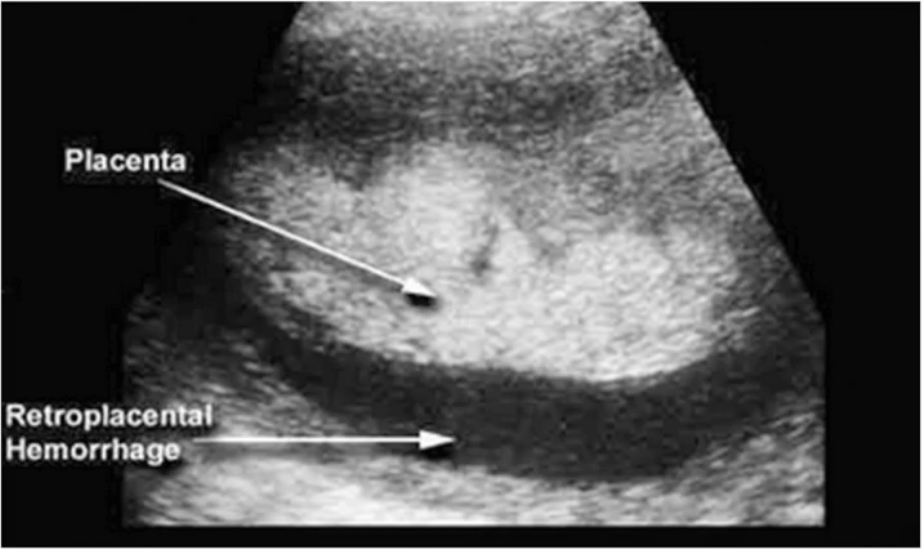

Paciente com DPP e o seguinte achado no US. Qual o achado ?

A

Hematoma Retroplacentário